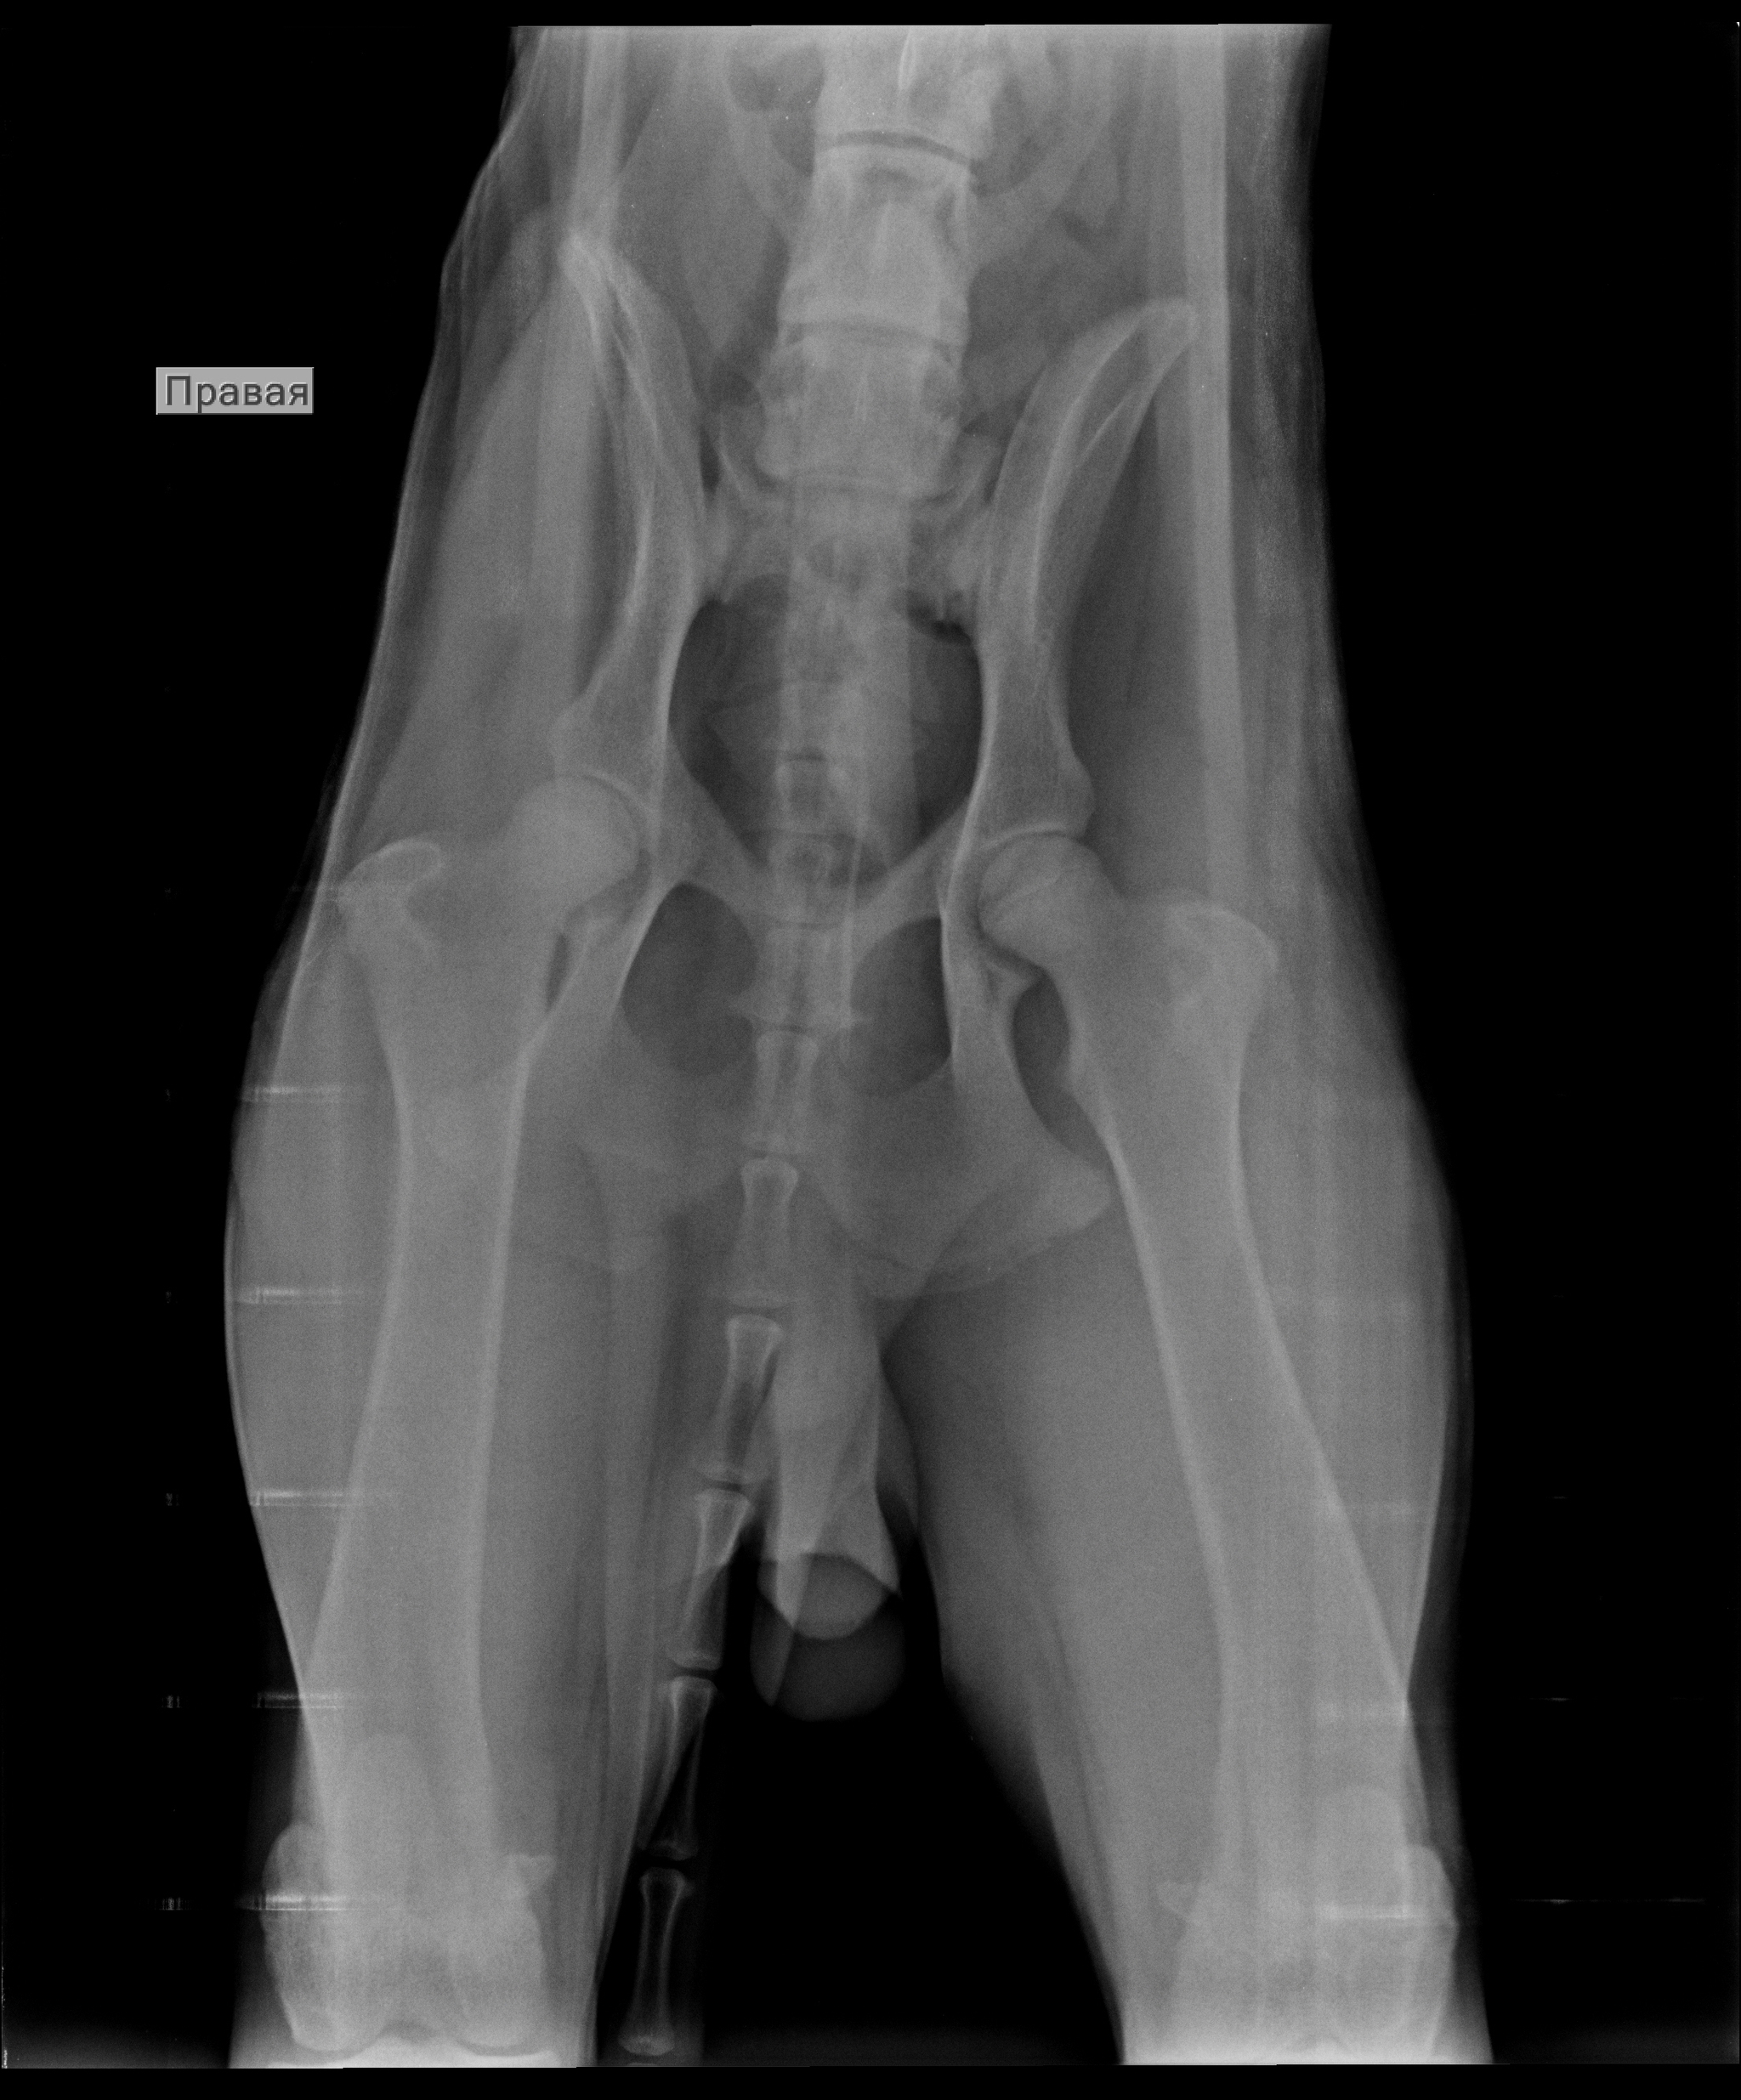

Выше представлены рентгенографические снимки котенка, которого ранее кормили кашей и мясом, а затем перевели на промышленные корма. Разница в 5 месяцев. Может показаться, что изменилось качество снимка за счет смены аппарата, например, или фотошопа :), но нет. На втором снимке заметно выше плотность кости.